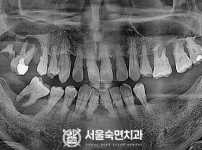

임플란트-전후사진4